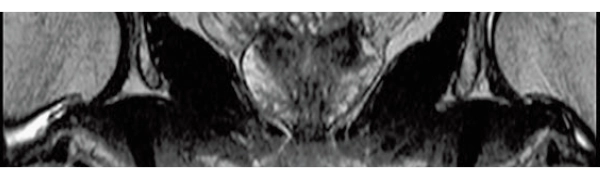

3DisoFSE T2WI

0.75×0.75×1.1(0.55)mm

MPR COR